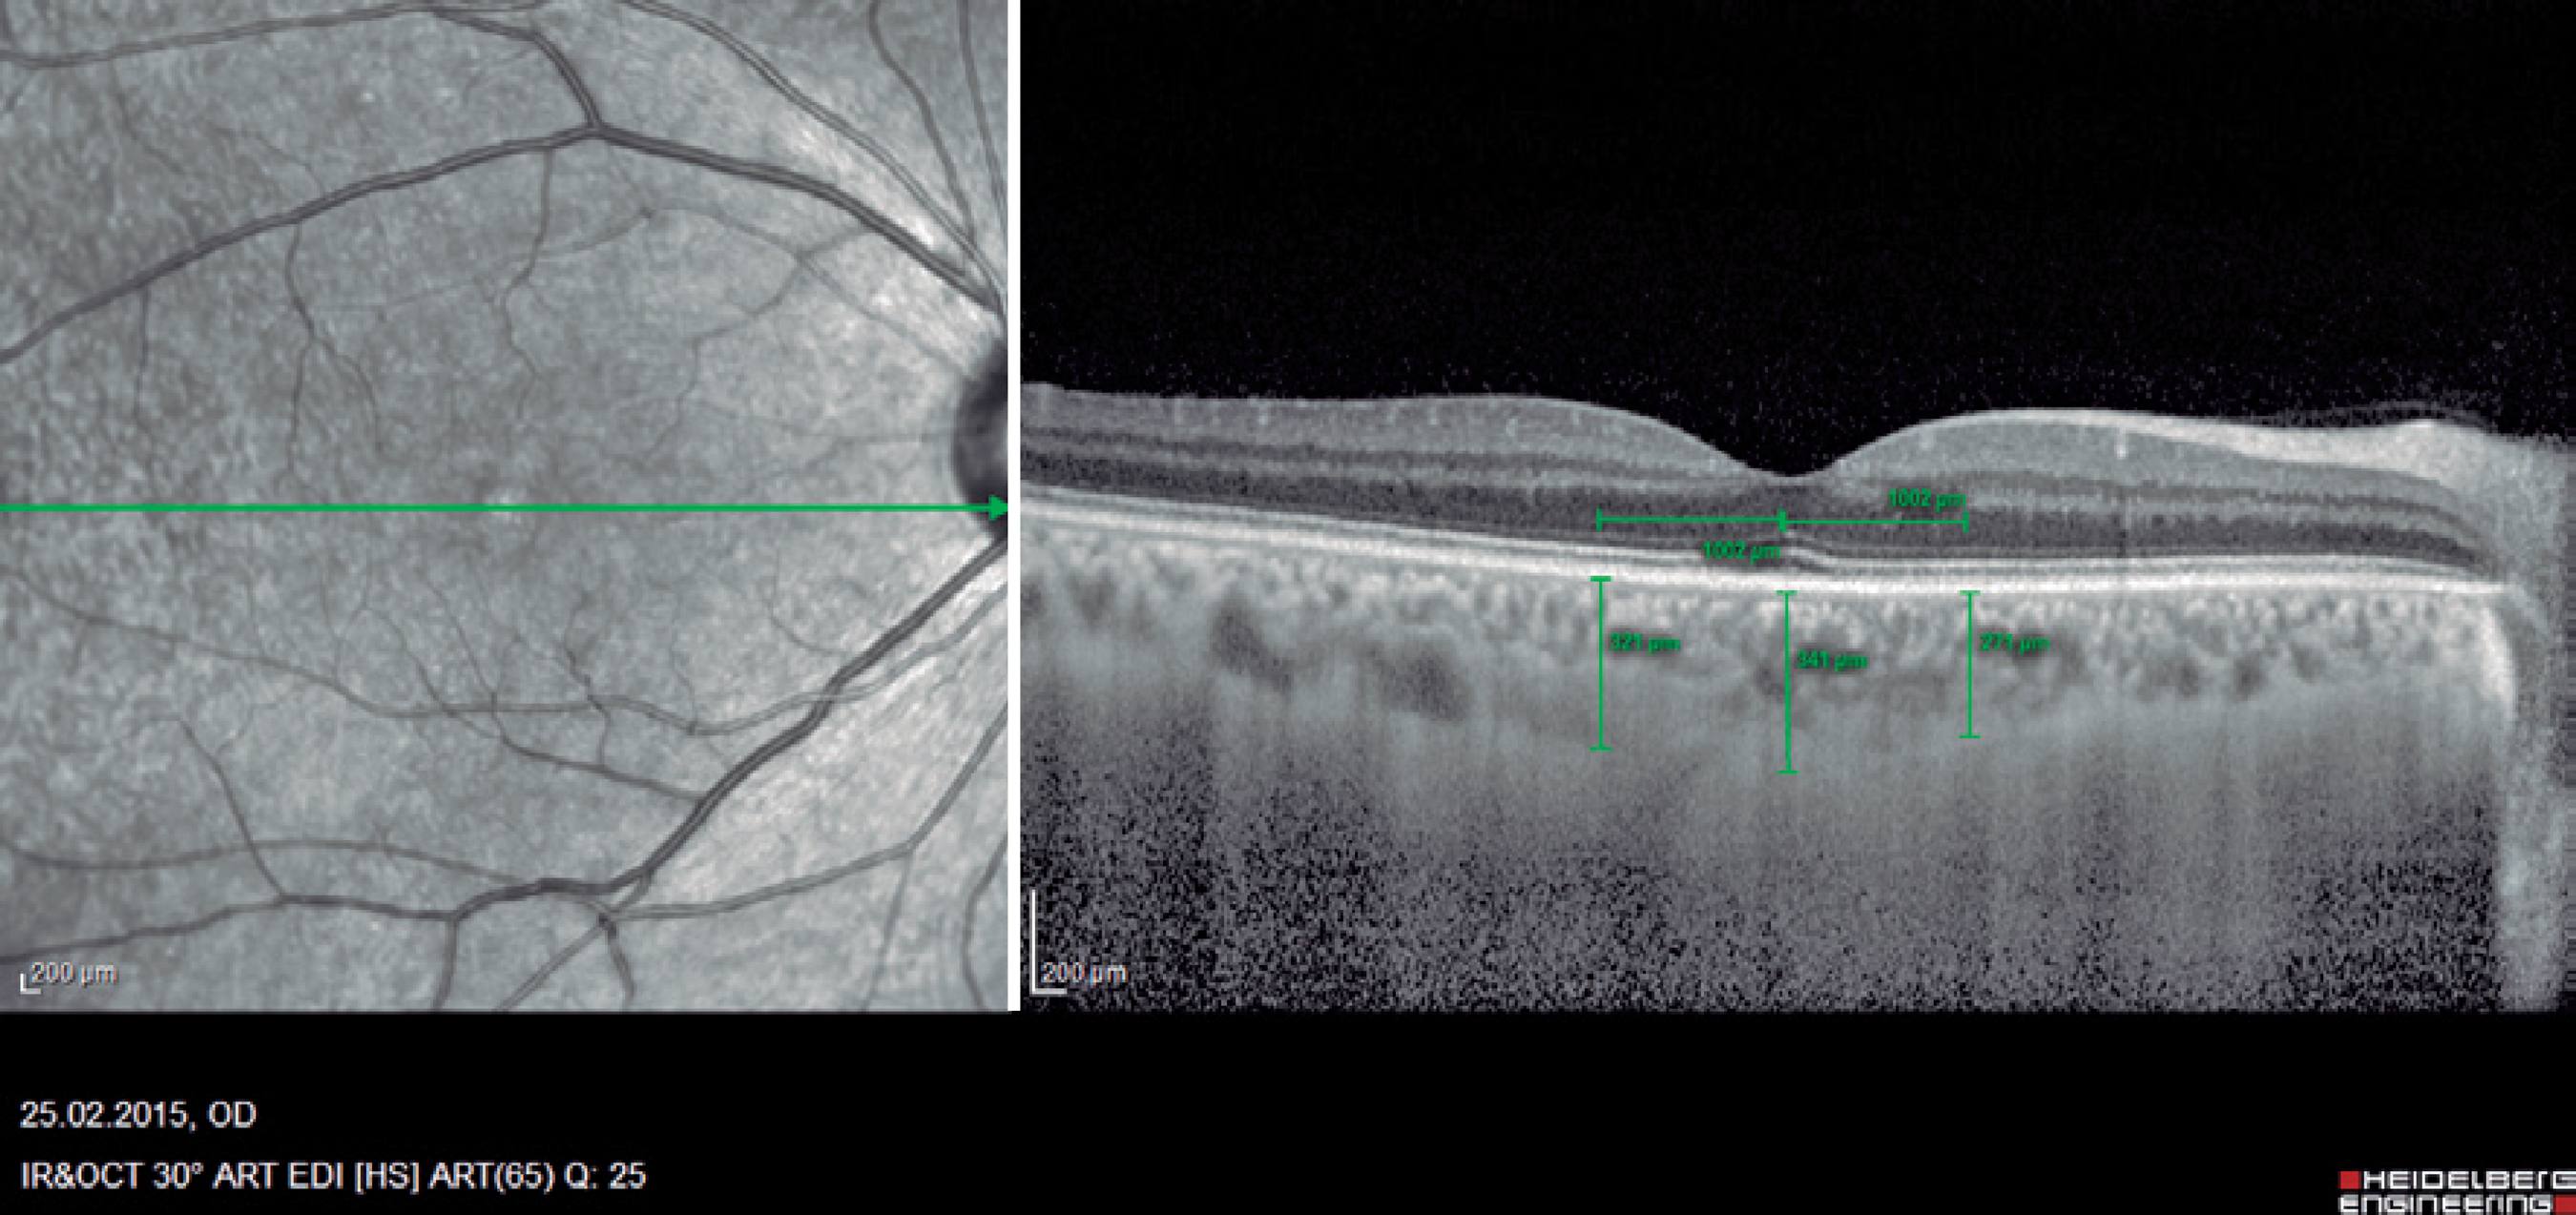

The central macular thickness (CMT), RNFL thicknesses, and choroidal thickness (CT) measurements were obtained using the Spectralis SD-OCT (Heidelberg Engineering; wavelength: 870 nm) with the enhanced depth imaging modality that has previously been described) (Figure 1)(16). All subjects were imaged by the same experienced technician. The central subfoveal choroidal thickness (CSCT), temporal choroidal thickness (TCT; 1 mm temporal CT from the fovea), and nasal choroidal thickness (NCT; 1 mm nasal CT from the fovea) were measured by two clinicians (I.Y. and E.P.) in a blinded manner, without knowledge of information of the subjects, and the mean of their measurements was used in the analysis. Measurements with a difference larger than 10% between the clinicians were excluded from the study. The peripapillary RNFL thickness parameters were automatically calculated using the same SD-OCT device and divided into regions including nasal (N) quadrant thickness (90º), nasal superior (Ns) quadrant thickness (45º), nasal inferior (Ni) quadrant thickness (45º), temporal (T) quadrant thickness (90º), temporal superior (Ts) quadrant thickness (45º), temporal inferior (Ti) quadrant thickness (45º), and mean (G) thickness (360º) (Figure 2). To minimize the possibility of choroidal changes attributable to diurnal choroidal fluctuations(17), all scans were performed during the same time of the day between 11:00 a.m.-12:00 p.m.

Figure 1 Example of enhanced depth imaging-optic coherence tomography measurements. Central subfoveal choroidal thickness (CSCT), temporal choroidal thickness (TCT; 1 mm temporal CT from the fovea), and nasal choroidal thickness (NCT; 1 mm nasal CT from the fovea).